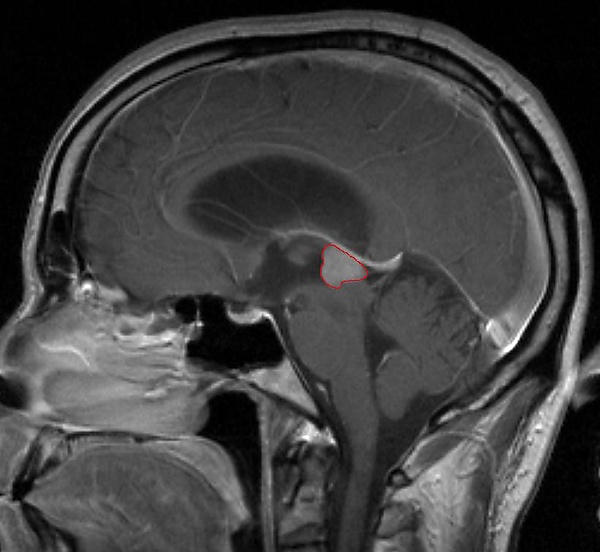

Пинеалома — опухоль головного мозга, исходящая из шишковидного тела. Это гетерогенная группа новообразований, локализующихся в пинеальной области (задние отделы III желудочка, область цистерны четверохолмия) и имеющих различное происхождение. Развитие пинеаломы может быть связано с опухолевой трансформацией пинеалоцитов, астроцитов или гоноцитов[2][3]. Опухоль, развившаяся из пинеалоцитов, в зависимости от степени дифференцировки носит название пинеоцитома, пинеальная паренхиматозная опухоль промежуточной дифференцировки, пинеобластома. Опухоли астроцитарного происхождения имеют типичное строение. Наиболее характерным для астроцитомы является медленный, инфильтративный рост.

Симптомы опухоли обусловлены её расположением. Наиболее частыми симптомами являются головные боли, тошнота и рвота. Они обусловлены повышением внутричерепного давления вызванного обструктивной гидроцефалией, которая возникает при сдавлении опухолевой массой водопровода мозга и нарушением циркуляции спинномозговой жидкости.

Компрессия верхнего двухолмия опухолью приводит к синдрому Парино — невозможности вертикальных движений глаз, небольшой дилатации зрачка. Возможно развитие отёка соска зрительного нерва